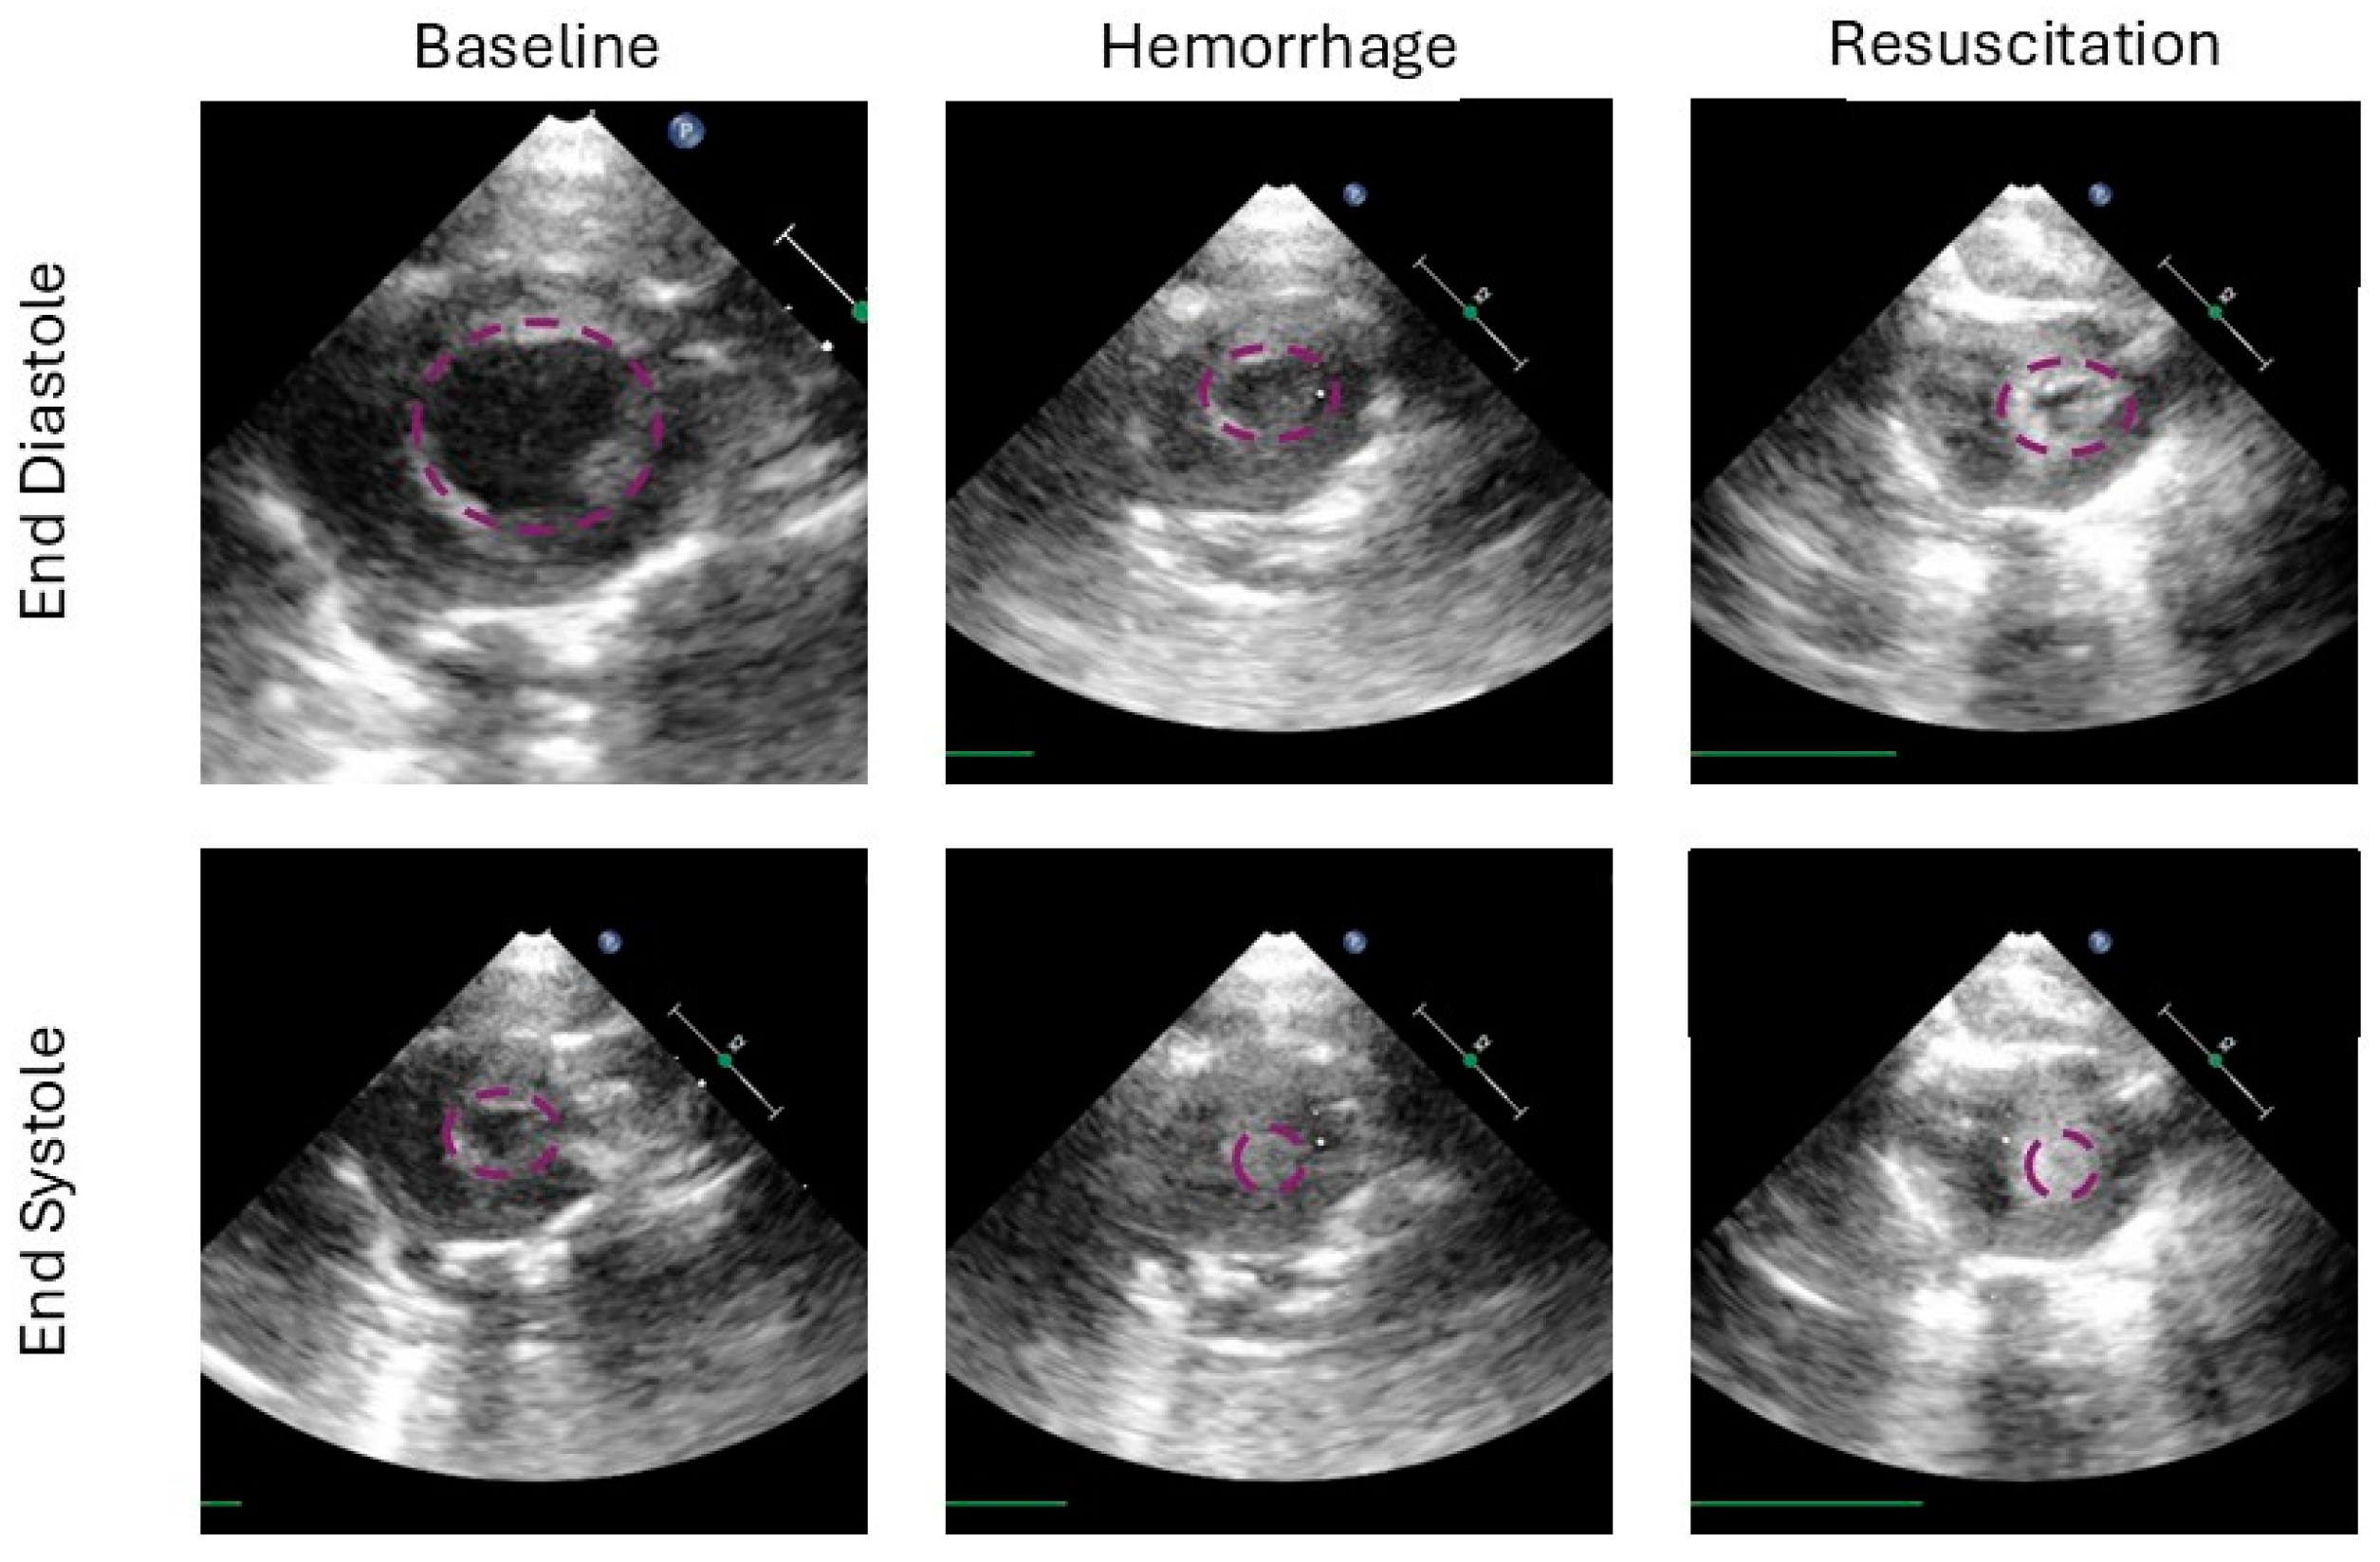

Fractional area change is the 2-dimensional equivalent to the commonly assessed left ventricular ejection fraction. FAC aims to assess left ventricular function, while CO assesses both ventricles combined. There was no significant correlation between independent variables and FAC at end-experiment in survivors, p = 0.56, 0.6, and 0.67 for hemorrhage time, down time, and FiO2; Figure 5.

The strength of this study may also be its limitation. Here, we evaluate many groups to tease apart how the hemorrhage and down time components contribute to the ‘golden hour’. To achieve this required a small N per group, 3–4. While our groups were evenly matched at baseline per our analysis of basal characteristics, there was a significant variation in survival and time to death within groups of the same treatment. This could have been improved with more repetitions, which was not feasible in the current study. Given the complex structure of this study, no traditional sample size calculations were performed a priori. Resultant to this, several calculations were left with a power below 0.8, therefore, type II error in the case of a negative result cannot be excluded. Alternatively, the limitation of two hours of post resuscitation time may have limited a survival signal that could have appeared later on. However, there were high homogeneity levels in lactate and MAP at end-experiment within groups, which are commonly assessed markers in trauma and shock models. Furthermore, this study added the first assessment of cardiac end-organ ischemia assessed with transthoracic echocardiography in a severe hemorrhagic shock model, Figure 6. By assessing left ventricle function and cardiac output in these models, future studies can evaluate systemic vascular resistance after resuscitation, which may be altered from post-ischemic vasodilation and any myocardial damage from hypoperfusion. What we have taken away from the left ventricular evaluation, is that after resuscitation the end-diastolic diameter did not return to baseline, and the FAC remained elevated. This is indicative of continued ‘hypovolemia’, which in our tightly controlled closed system study, means that the ischemia–reperfusion after hemorrhagic shock results in a vasodilatory response or to third spacing and tissue swelling to a significant degree. We believe the former to be more significant given the time frame of this study. This has repercussions for trauma resuscitation, meaning that normovolemia or normalizing left ventricular end diastolic diameter may not be reflective of the patient’s true baseline volume status. Lactatemia and acidosis after reperfusion should be evaluated in the overall picture and some vasoconstrictive agents may be appropriate if hypervolemia is to be avoided. Notable hypervolemia in the perioperative space is well studied and linked with poor outcomes [19]. That controlled setting may be less severe than what we see in this study.

Figure 6. This figure demonstrates the left ventricle in end diastole (top row) and end systole (bottom row) at several time points in the study (from left to right: baseline, at the end of hemorrhage and the end of the experiment after resuscitation). The baseline columns show a robust end diastolic volume, and a residual cavity in systole. Ventricular area is highlighted in purple for each image. After hemorrhage, the ventricle is underfilled and the systolic cavity is not present, representing 100% ejection. In the resuscitation column we see residual underfilling, however, semblance of a cavity can be seen, suggesting either cardiac injury, ongoing reduction in preload, or a combination.